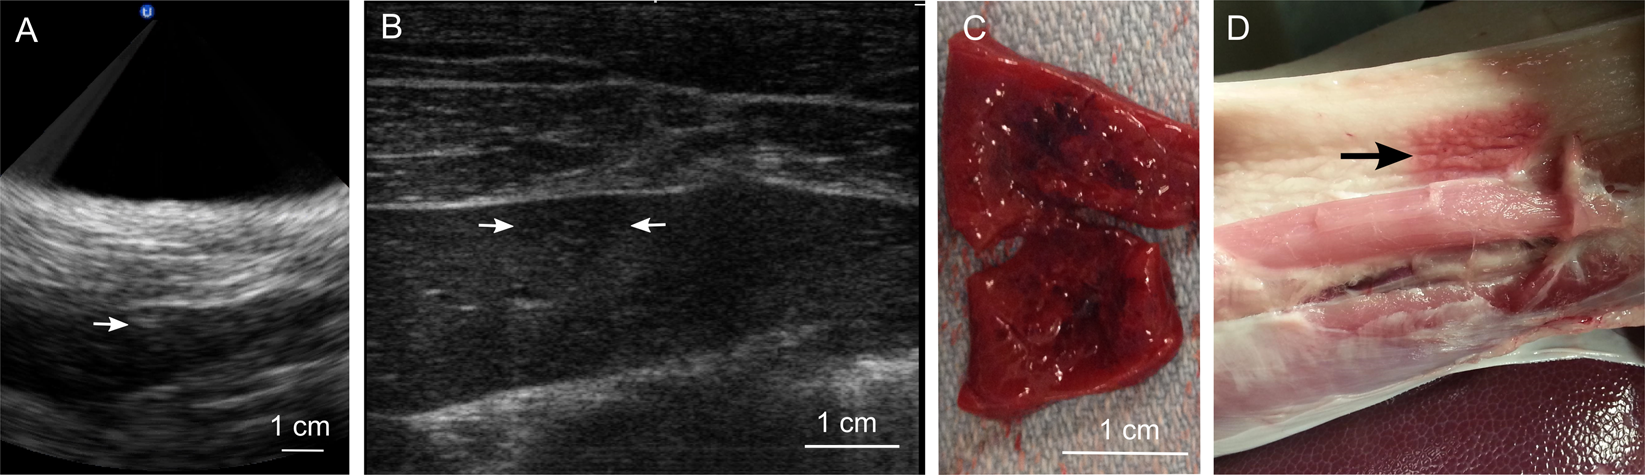

Investigation of feasibility and safety of volumetric BH treatment of porcine liver. (A) B-mode ultrasound image guidance during treatment of the liver. The white arrow indicates the location of the hyperechoic region at the focus, which was much less discernible than that in kidney treatments. This is likely due to the aberrating effects of fat-containing body wall overlying the liver. (B) Post-treatment ultrasound evaluation of the treated area. The hypoechoic region of ~1 cm size corresponding to the liquefied area is marked by the two white arrows. As seen, the liquefied region was almost indiscernible in liver and much less defined than that in kidney. This could be due to the aberrating effects of the body wall degrading image quality and/or due to the incomplete loss of structure and retention of the lobular compartments in the ablated area (see below). (C) A representative gross view of the bisected liquefied lesion in the liver. (D) A representative gross view of the body wall overlying the treated liver. The arrow marks what appears to be a mix of mechanical and thermal damage to the fatty layer of the body wall. This collateral damage was observed in three out of the four treated livers.